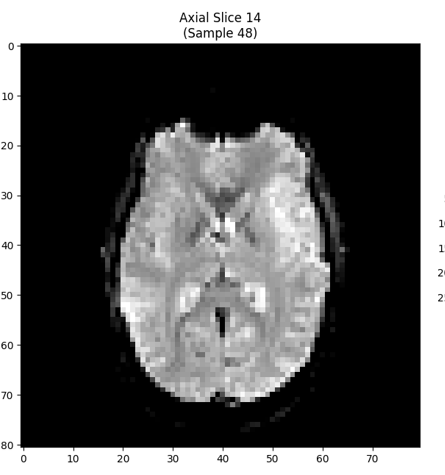

fMRI Analysis of Visual Motion Stimuli

In this assignment, I processed 4D fMRI data to examine brain responses to coherent, incoherent, and biological motion. I created voxel‑wise correlation maps aligned with stimulus timing, both with and without hemodynamic response modeling. The results showed expected activation in the primary visual cortex for all motion types, but biological motion uniquely engaged regions such as the superior temporal sulcus and middle temporal gyrus. I concluded that these findings align with prior research, highlighting the brain’s specialized sensitivity to biological motion.